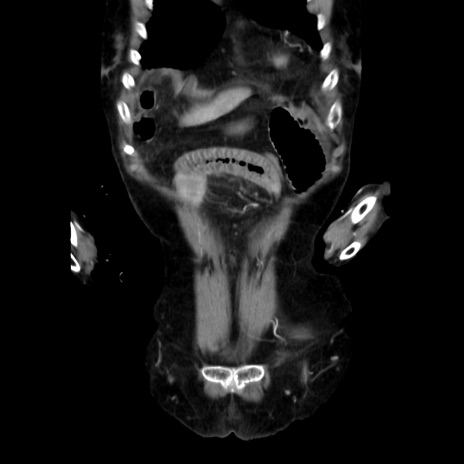

症例40(冠状断像)

【症例】90歳代女性

【主訴】腹痛・嘔吐

【現病歴】 食欲低下、嘔吐があり昨日他院受診。肺炎と診断され入院となる。入院後より腹部全体に圧痛あり。胃管留置され経過みていたが、症状持続するため、

当院転院となる。

【身体所見】腹部:中央に激痛あり、圧痛あり、反跳痛不明

【データ】WBC 17100、CRP 18.82

冠状断像